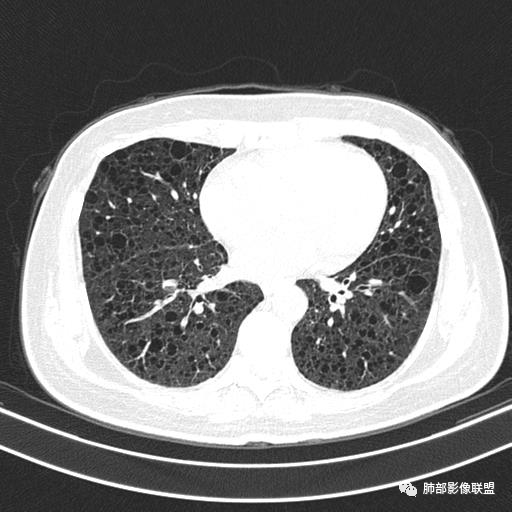

双肺弥漫囊腔,累及肋膈角,囊腔形态相对规则单一。

CT平扫示双肺弥漫分布大小不等囊状薄壁透光区,无内、中、外带分布差异,间质稍示增厚。拟LAM

中年女性育龄期妇女,咳嗽气喘,无吸烟史,有苯吸入史。影像:双肺弥漫均匀小囊腔,无明显分布优势,囊腔形态欠规则,壁薄,部分囊腔边缘血管征,伴双肺弥漫磨玻璃影,无结节,考虑lam,鉴别苯中毒肺损伤,囊腔多有分布优势,小叶中心分布为主,形态规整等

女,46,活动性气喘1年。苯吸入史半年。胸部CT:两肺弥漫囊腔,上至肺尖,下至肋膈角,形态类似小囊腔。考虑:LAM,鉴别LIP,BHD,PLCH等。

CT表现:双肺弥漫大小不等的薄壁囊腔,囊壁<2mm,外形规则,血管影多位于囊腔周围,囊腔之间肺组织正常,随着疾病进展到晚期,囊腔变大、增多,不可胜数,囊腔可融合成较大的囊,与肺气肿相似,形成间质性肺纤维化。部分病例可出现结节影。